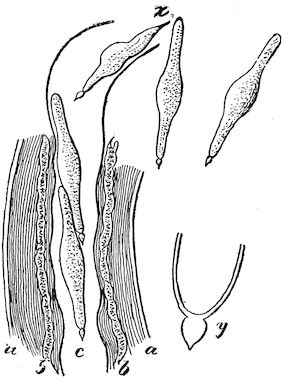

(2.) The horn-secreting membrane is formed by the skin, which undergoes special development around the base of the horn and comes to resemble that of the coronary band, from which the hoof or claw is secreted. The band is about one-fifth of an inch in breadth. The papillæ of the dermis are specially developed at this point, and the epithelium which they secrete eventually forms the horn.

The internal surface of the growing horn is adherent to the horn core through the medium of another tissue formed by a specially differentiated periosteum which is continuous with the periosteum covering the frontal bone. It is not a true periosteum, but a vascular tissue formed of papillary layers analogous to those of the podophyllous tissue of the ox’s claw or horse’s hoof.

This keratogenous membrane receives a rich vascular supply from the arterial circle formed at the base of the horn core by a division of the external carotid, the blood conveyed by which is freely distributed to the enlarged papillæ. The great vascularity of these parts 23explains why lesions of the horns are often followed by such profuse bleeding.

(3.) The horn secreted by the papillæ of the horn band (which is analogous to that of the coronary band of the horse) forms a cone varying in its curve in various breeds. Its base is hollow, and contains little depressions holding the papillæ from which the horn is secreted. From its base up to the end of the horn core the walls progressively increase in thickness. From this point it is solid; in a fully-grown horn the bone does not extend more than one-half or two-thirds of the entire length.